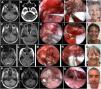

ResultsA number of 40 patients were included. The age average was 49.4 years and male/female proportion was 0.4–1. We found 31 vestibular schwannomas (77.5%), five meningiomas (12.5%), two cholesteatomas (5.0%) and two metastases (5.0%). Vestibular schwannomas Hannover type IIIb, IVa and IVb predominated. The surgical resection was total or near-total 92.5% of patients. Hearing preservation rate was 62.5% and acceptable facial function nerve function rate was 80% after six months. Hospital stay was 7.5 days. The total or near total resection and functionally preservation rate was high. Complications were unusual.

ConclusionsEndoscopic retrosigmoid keyhole approach represented a safe and efficient procedure in selected patients with cerebellopontine angle tumours.